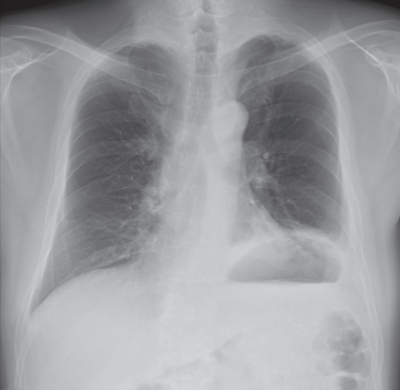

血液所見:赤血球 410 万、Hb 13.0 g/dL、Ht 40 %, 白血球 7,300、血小板 15 万。血液生化学所見:総蛋白6.5 g/dL、 アルブミン 4.5 g/dL、 総ビリルビン 0.6 mg/dL、 直接ビリルビン0.2 mg/dL、AST 20 U/L、ALT 25 U/L、LD 185 U/L(基準 120~245)、ALP 110 U/L(基準 38~113)、 尿素窒素 11 mg/dL、 クレアチニン 0.4 mg/dL、Na 140 mEq/L、K 4.0 mEq/L、Cl 101 mEq/L。CRP 2.0 mg/dL。 術前後の胸部エックス線写真を別に示す。

原因として考えられるのはどれか。

c. 横隔神経麻痺